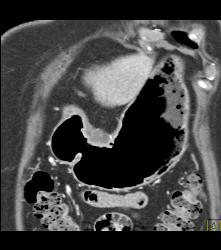

GIST Tumor